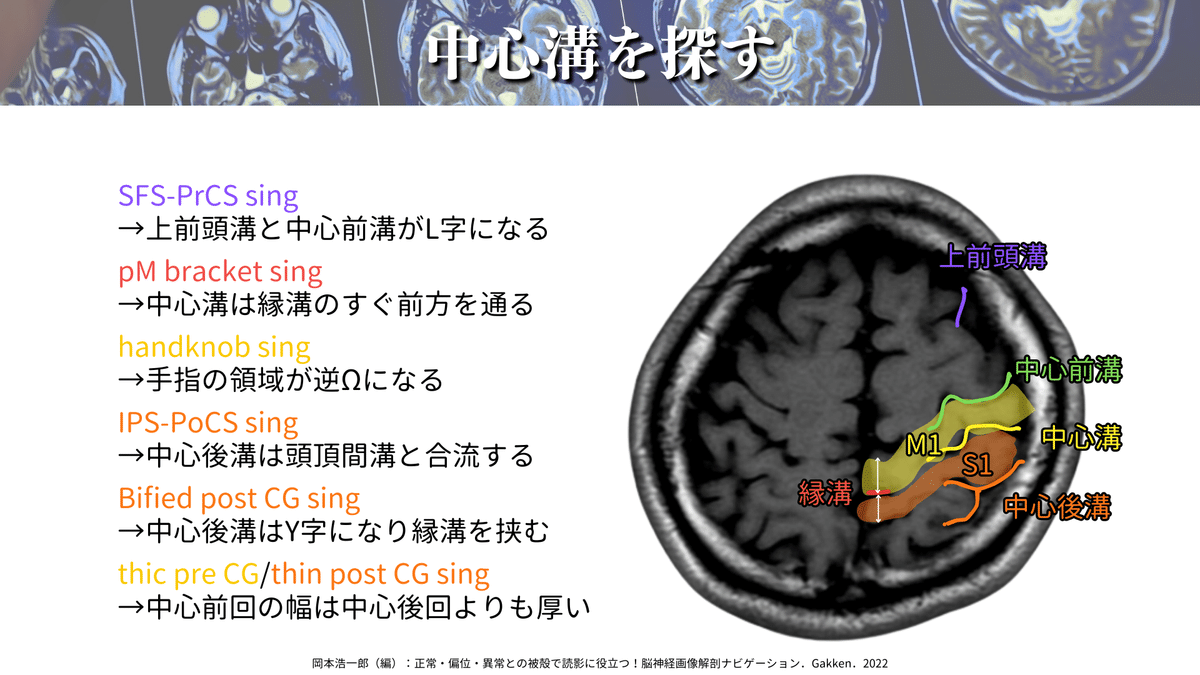

M1を探すなら、まずは「中心溝」を探しましょう!

⬇️のポイントを押えることで、ほとんどの場合に対応できるかと思います☝️

特に僕のおすすめは「pM bracket sing」「handkob sing」「Bified post CG sing」の3つです!

この3つだけでも結構な確率で見つけられますが、6つ全てを押さえておくとより安心かと思います👍

ここまでで、「中心溝」を見つけられたと思いますので、その前方にある「中心前回(M1)」も見つけられたと思います✨